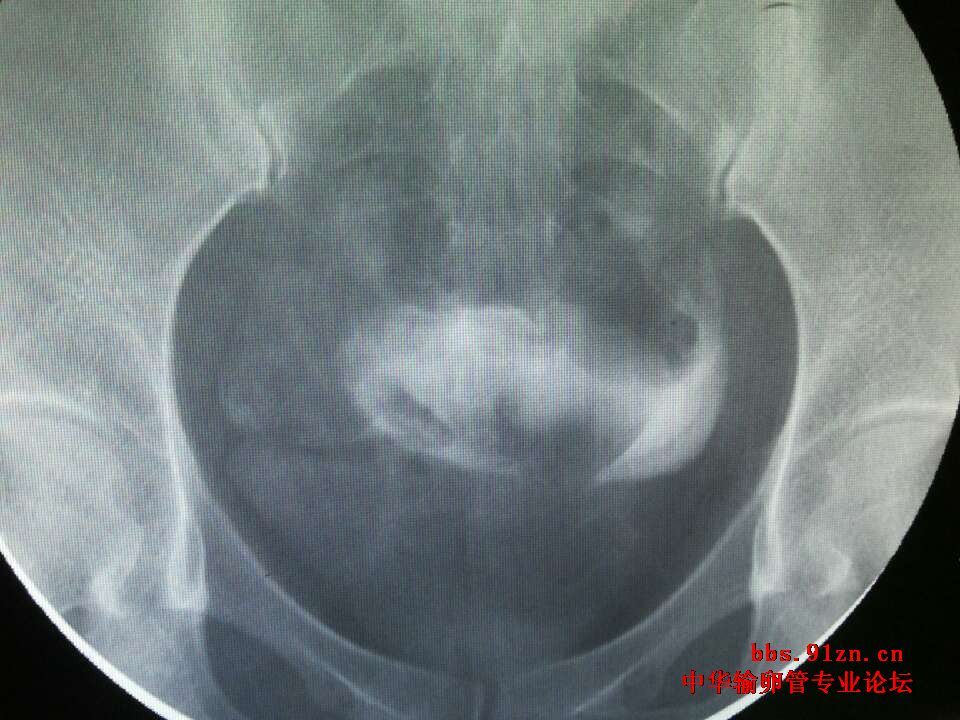

请大夫看看输卵管造影片

年龄:(29 )岁 ;近期查出多囊卵巢综合症,左右各11.12个卵泡,小于6mm 已经试孕( 半)年; 平时月经周期不准,月经持续3 天; 既往怀孕(1   )次,流产( 1)次药流,最近一次流产距今(5  )年; 男方的精液检查结果( a+b=40%,a18%);

您的片子上没有标左右,您有一侧没有显影,显示阻塞,或者是切除过一侧输卵管,另一侧虽然通畅,但是略有些粘连,但是您不怀孕的主要原因是多囊的问题,卵巢不排卵肯定怀不上孕,您这种该情况可以手术治疗,一是治疗多囊,二是探查另一侧不通的,通的那侧粘连可以分解开,没有其他问题术后第二个月就有自然受孕的机会。